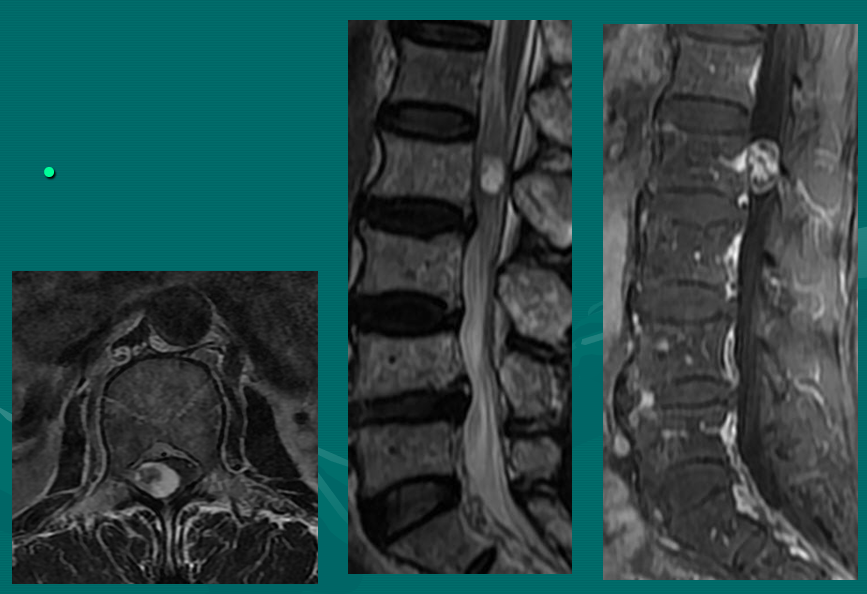

腰椎间盘突出

腰椎间盘突出分型:以椎间盘疝出物突出的方向分为四型,即中央型、外侧型、远外侧型和侧前型,前两种为椎管内型,后两种为椎管外型。

中央型椎间盘疝出物位于椎管中部主要对硬膜外脂肪间隙和硬膜囊形成压迫;

外侧型椎间盘疝出物位于椎管内一侧,未超过椎间孔内口,主要对硬膜外脂肪间隙、硬膜囊和神经根形成压迫;

腰椎间盘脱出

腰椎间盘脱出-髓核游离